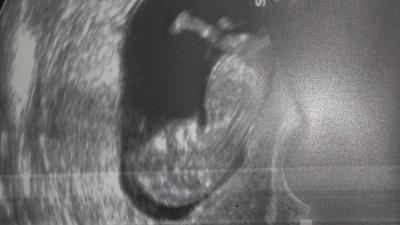

Bin ganz aufgeregt und über GLÜCKLICH. Hatte beim Ultraschall Tränen in den Augen. Es hat gestrampelt wie ob es ein Kickboxer oder Kickboxerin gibt. Es ist alles in Ordnung.

Bild zu Frauenarzt besuch - Forum für Januar - Mamis